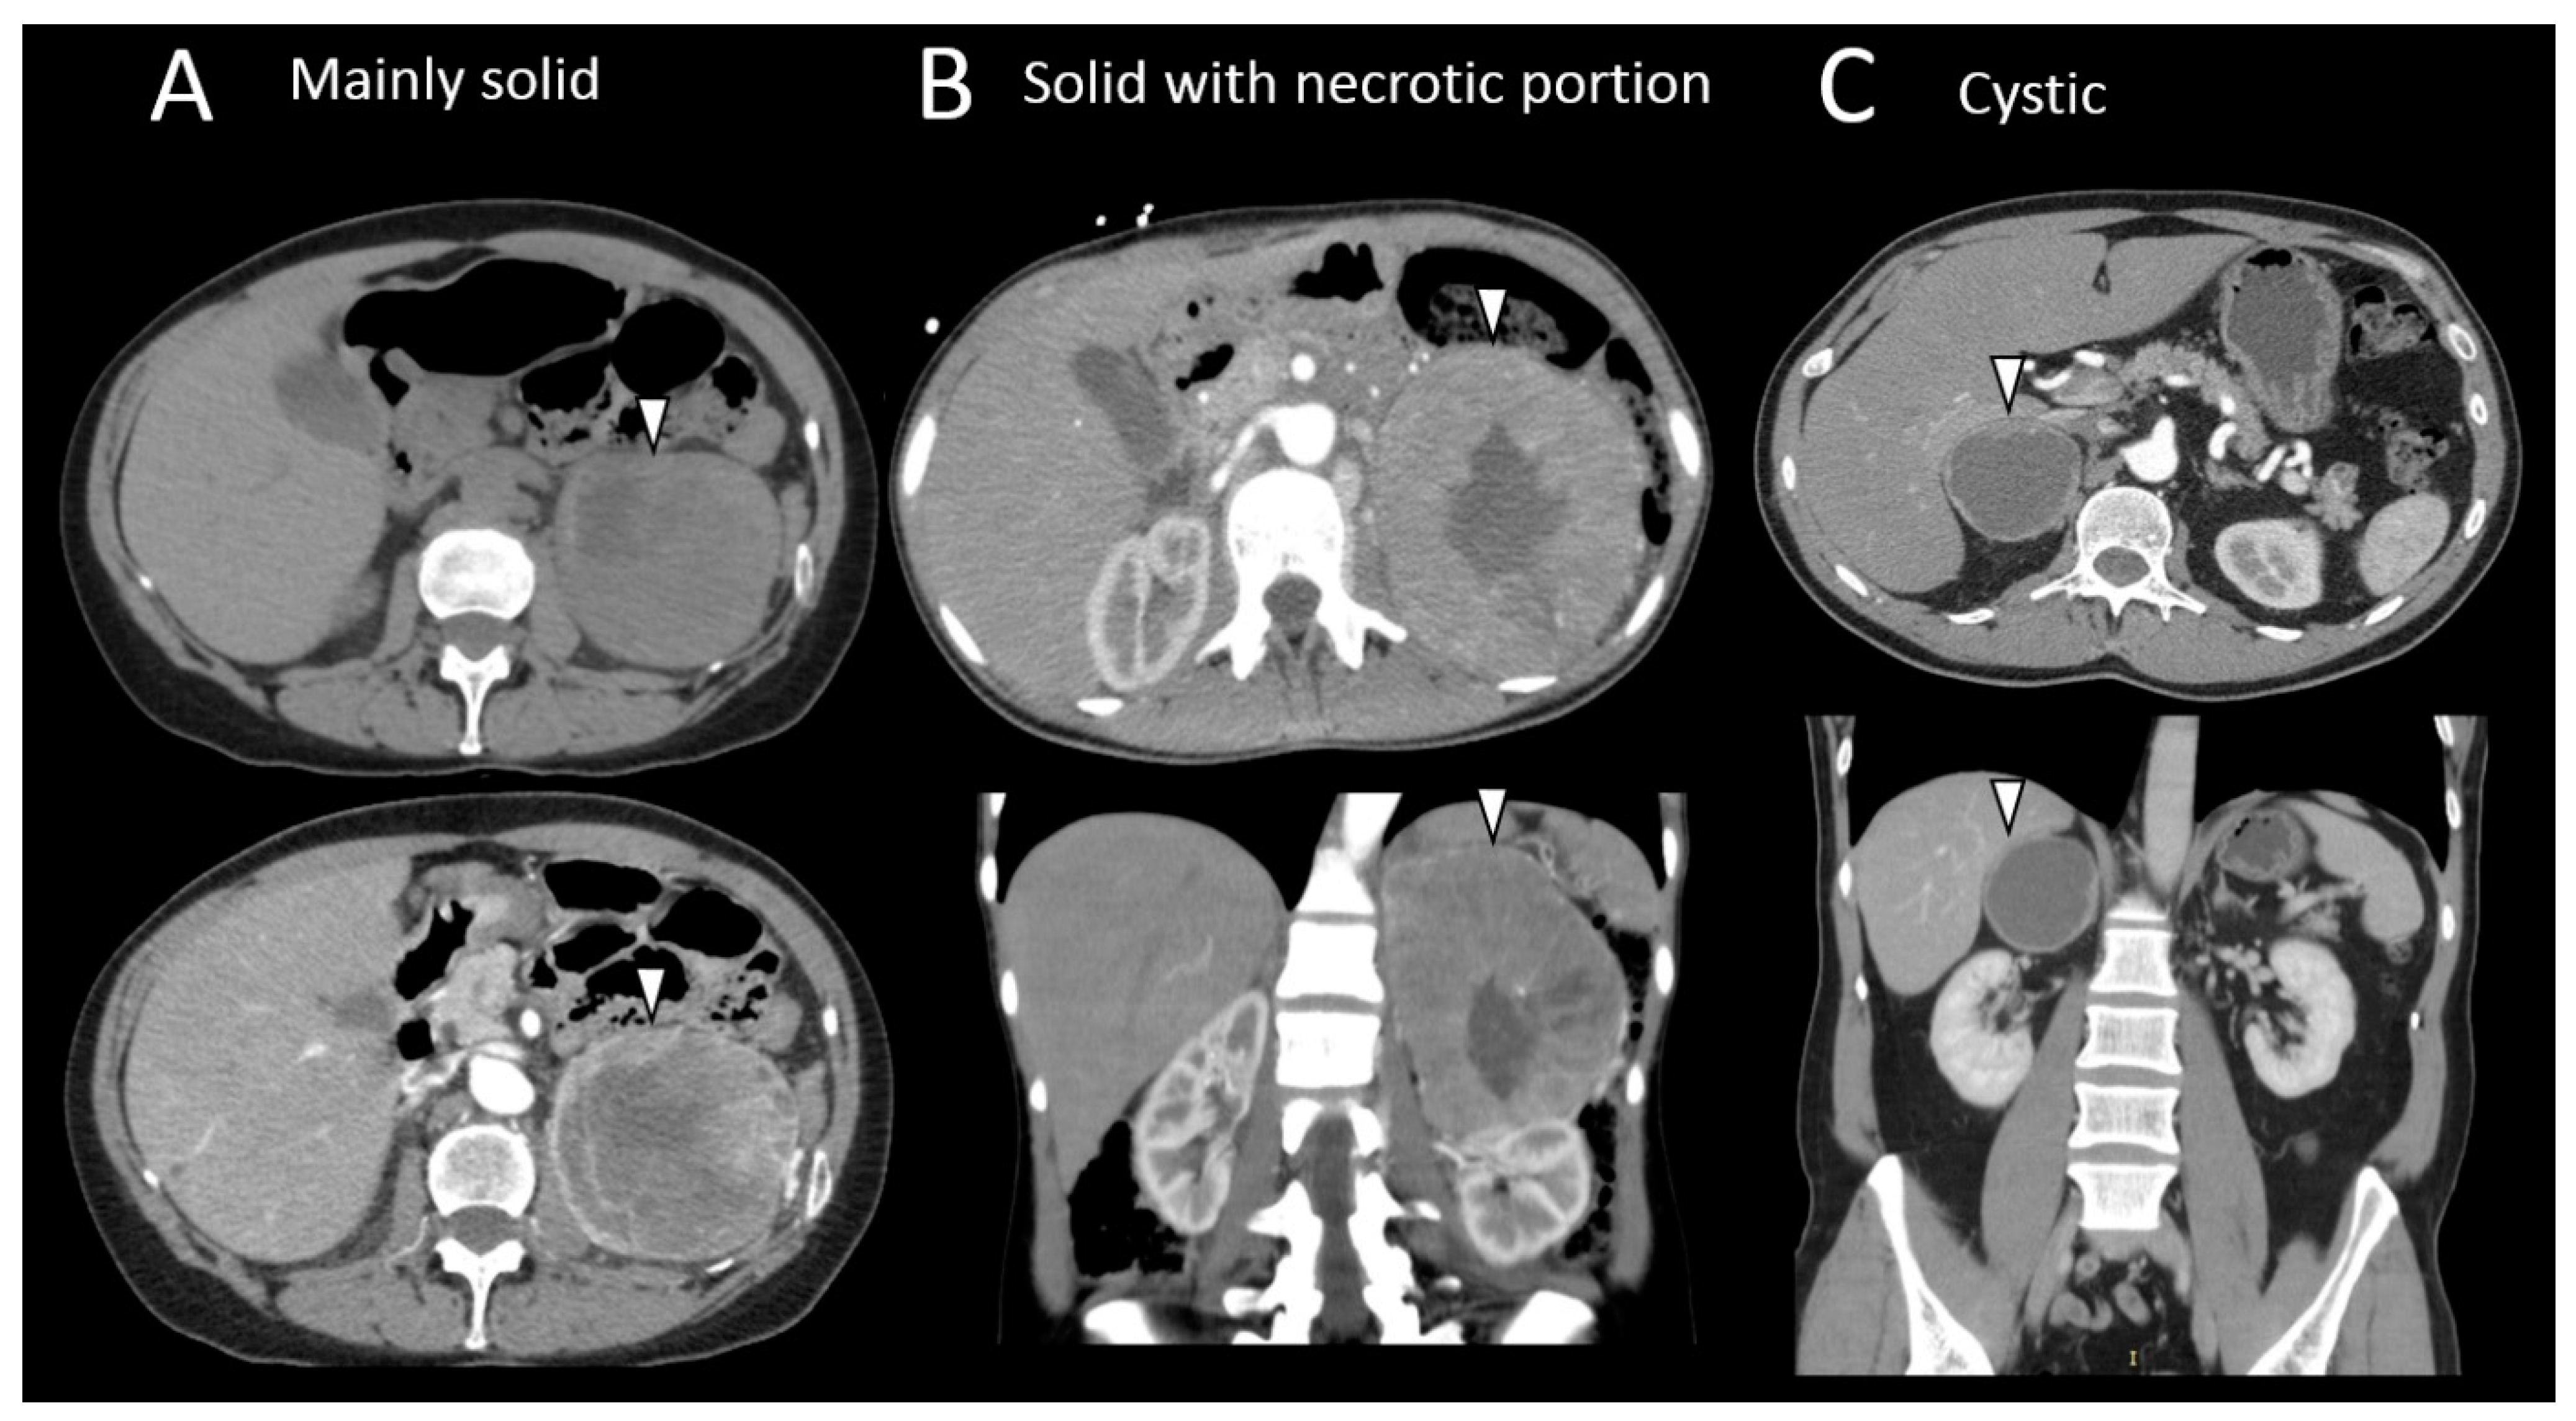

3.4. Pheochromocytomas and Paragangliomas: Variable Morphological Characteristics Using Anatomical Imaging